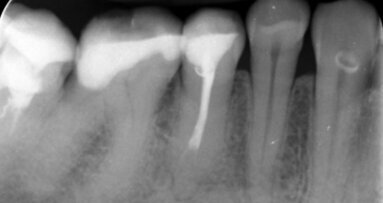

Sięgnęłam więc po laser LightWalker erbowo-jagowy – założyłam końcówkę kontaktową Precisio 300/14 (niestety, nie użyłam końcówki PIPS, bo jej jeszcze nie posiadam, a pewnie byłaby to dla mnie końcówka z wyboru). Ustawiłam następujące parametry: tryb MPS 250 mJ, 20 Hz. Jeden impuls: pacjentka poczuła nieznaczny ból, a kanał był już udrożniony (Ryc. 3). Wypełniłam kanał (Ryc. 4), a dolegliwości bólowe się skończyły.